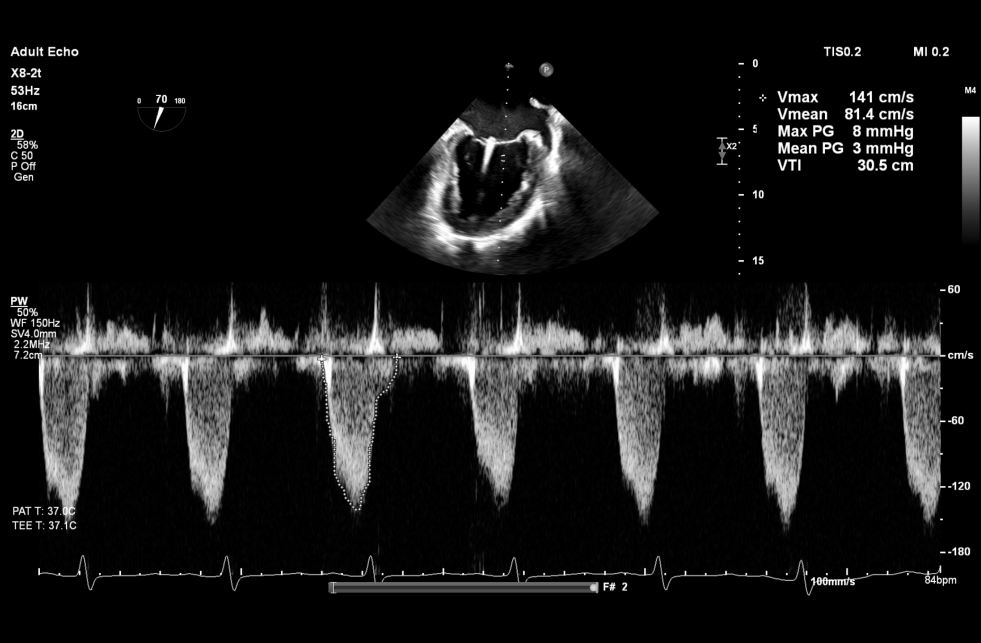

术后Xplane彩色图像

夹合后二尖瓣反流量0+,平均跨瓣压差3mmHg